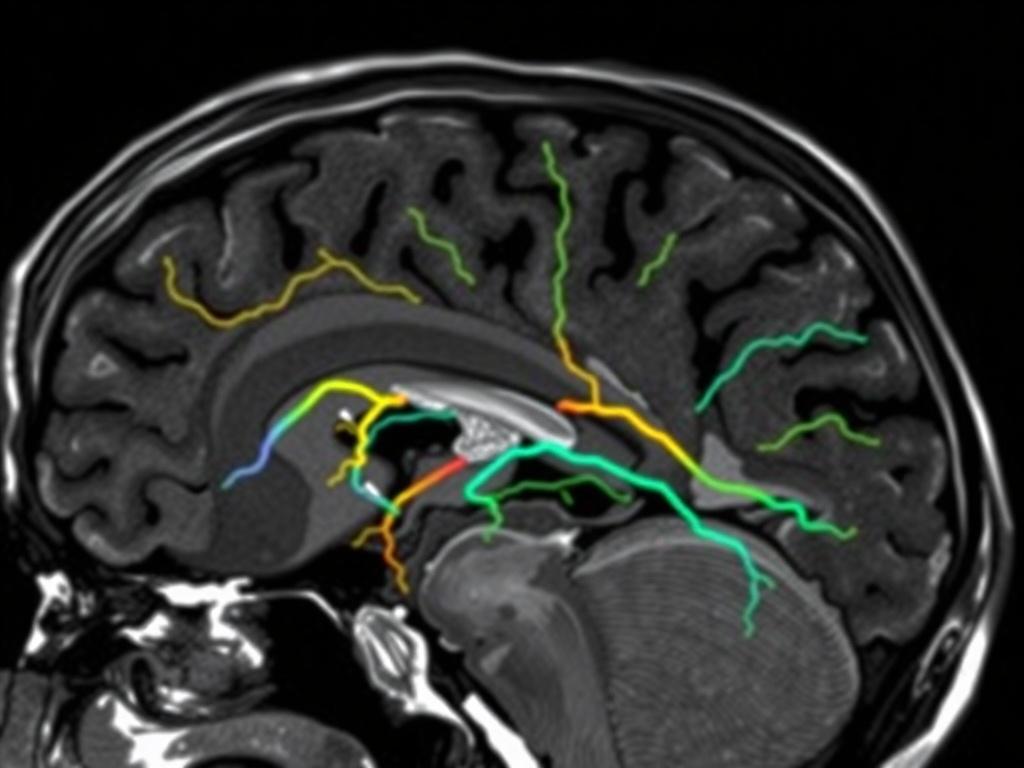

ТКДС соединяет два режима ультразвука. Первый рисует картинку сосудов. Второй измеряет скорость и направление кровотока. Врач смотрит через «ультразвуковые окна» в тонких участках черепа: виски, затылок, подзатылочная область, иногда глазница. Эти зоны лучше пропускают ультразвук, поэтому аппарат получает четкий сигнал.

УЗДГ и дуплекс артерий шеи показывают кровоток в сонных и позвоночных артериях вне черепа. ТКДС оценивает внутричерепные сосуды: среднюю, переднюю и заднюю мозговые артерии, основной ствол, позвоночные артерии в интракраниальном сегменте, венозные синусы. Часто врач назначает оба исследования. Так складывается полная картина пути крови: от дуги аорты до мелких ветвей в мозге.